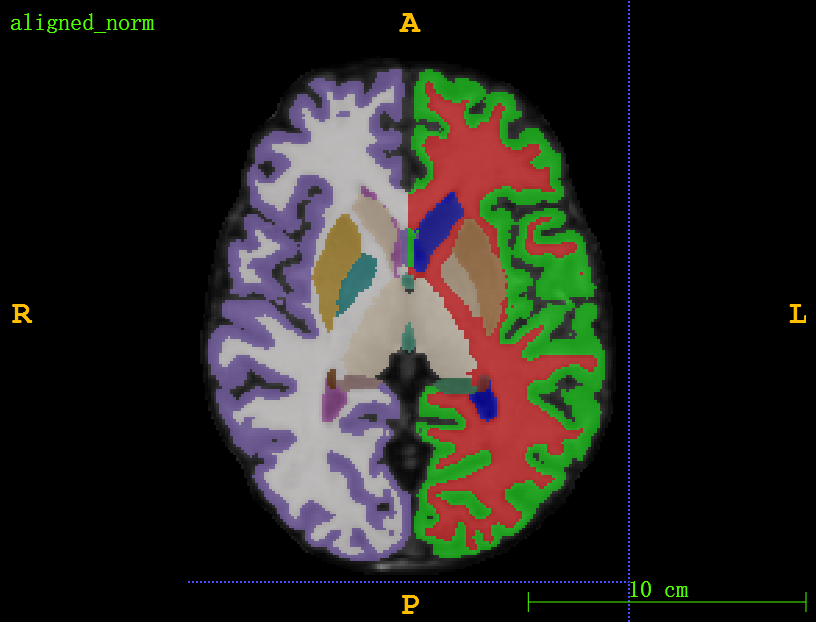

Task 03: Whole Brain MRI

Whole brain MRI showing important neuroanatomical regions: cortical, subcortical and deep brain structures. Highly accurate alignment of subcortical and deep brain anatomy across patients within the same modality (MRI)

40 个小结构(皮质下和脑深部)的自动自由曲面分割,手动验证。所使用的软件是 FreeSurfer 7.1 和 SAMSEG。

Common pre-processing to same voxel resolutions, intensity normalization, and spatial dimensions as well as affine pre-registration will be provided to ease the use of learning-based algorithms for participants with little prior experience in image registration.